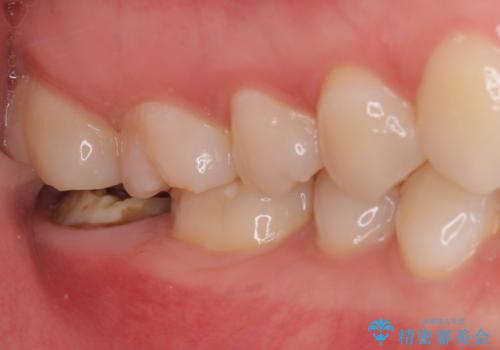

- 奥歯のかぶせものが頻繁に脱離することを気にされて来院された患者様です。

歯の高さが低く、かぶせものを安定して維持させることができないため、歯冠長延長術により歯の高さを増大させた上で、オールセラミッククラウンにて補綴することとしました。

クラウンが外れている期間も長く、虫歯が進行していたため、根管治療も行うこととしました。